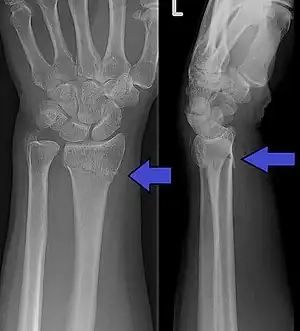

Fratura de Colles

A fratura de Colles é a fratura da extremidade distal do rádio, onde o fragmento se desloca para trás e para o exterior.

Tem como característica o aspecto da mão como o dorso de um garfo.

O principal diagnóstico é feito pelo raio-X (radiografia).